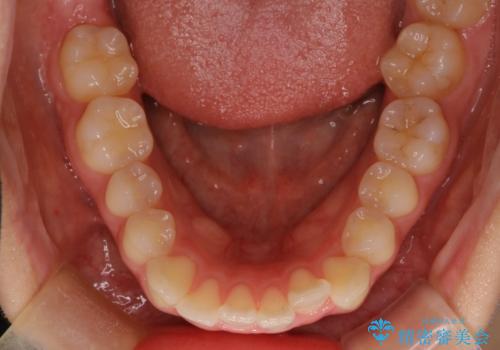

- 前歯が出ていることを主訴に来院されました。

奥歯を後ろに動かしながらスペースを作ることで、前歯を下げることができ患者さんにも満足していただきました。